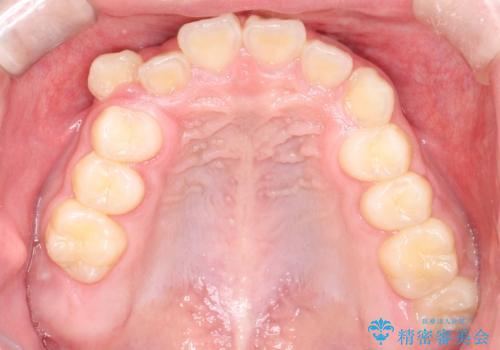

八重歯・歯並びのデコボコとディープバイトを改善した抜歯ワイヤー矯正症例

矯正の精密検査の結果上顎左右4番の計2本を抜歯し、審美性に配慮したワイヤー矯正装置(審美装置)を用いて治療を行いました。

八重歯などの歯列のデコボコが綺麗に改善され、患者様にも大変喜んでいただけました。また、咬み合わせが深い「ディープバイト」も併せて改善し、見た目だけでなく機能面でもバランスの取れた咬合を獲得しています。